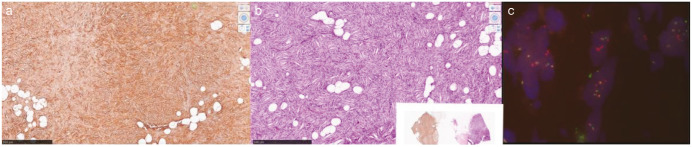

摘要隆突性皮肤纤维肉瘤(DFSP)是一种罕见、低级别、源自真皮层的纤维母细胞间充质肿瘤。乳房是一个罕见的部位,发病率仅为0.8-4.5%,在任何部位的总体发病率为4.2-4.5 /百万人。手术切除2-3厘米的边缘是金标准治疗。选定的病例接受放疗或伊马替尼全身治疗。由于罕见的表现,我们报告一例类似的左乳DFSP病例,患者为42岁女性,她最初被诊断为左乳良性叶状瘤,最终的组织病理学报告显示广泛的局部切除标本诊断为乳腺DFSP。

Dermatofibrosarcoma protuberans (DFSP) is a rare, low-grade, fibroblastic mesenchymal tumor derived from the dermis. Breast is an uncommon site with an incidence of only 0.8-4.5% and an overall population incidence at any site of 4.2-4.5 per million. Surgical excision with 2-3 cm margin is the gold standard treatment. Selected cases are subjected to radiotherapy or systemic therapy with Imatinib. Due to the rare presentation, we report a similar case of DFSP on the left breast in a 42-year-old woman, who was initially diagnosed with benign phyllodes tumor of the left breast and final histopathology report of the wide local excision specimen diagnosed DFSP of the breast.